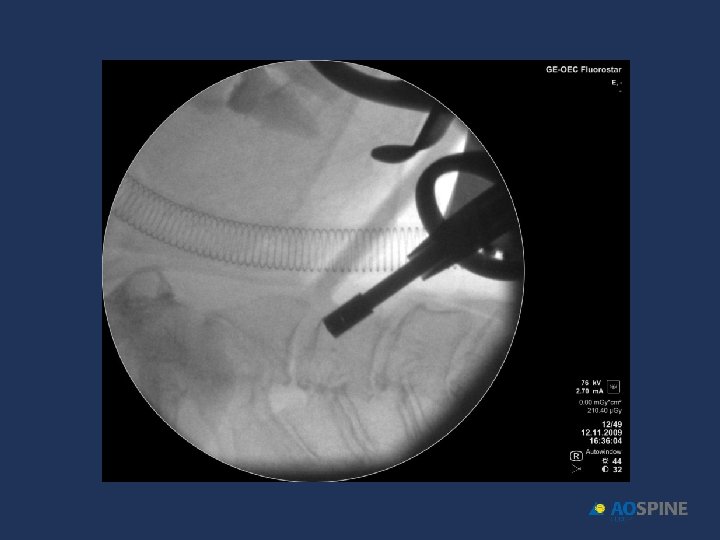

ODONTOID FRACTURES odontoid screw ADVANTAGES CONTRAINDICATIONS • PRESERVES MOTION C 1 C 2 • TRANSVERSE LIG RUPTURE • DONT NEED POSTOP HALO • EXTENSE C 2 BODY FX • DONT NEED BONE GRAFT • IRREDUCTIBLE FRACTURE • ANTERIOR OBLICUE FX

ODONTOID FRACTURES • RIGID COLLAR 10 -12 WEEKS • ONE SCREW • BEST RESULTS DURING FIRST 6 MONTHS AFTER FX Jenkins et al. J Neurosurg 1988, 89 Apfelbaum et al. J Neurosurg 2002, 93

ODONTOID FRACTURES odontoid screw • 90% FUSION TYPE II • 95% FUSION TYPE II < 6 MONTHS EVOL. • 100% FUSION TYPE III